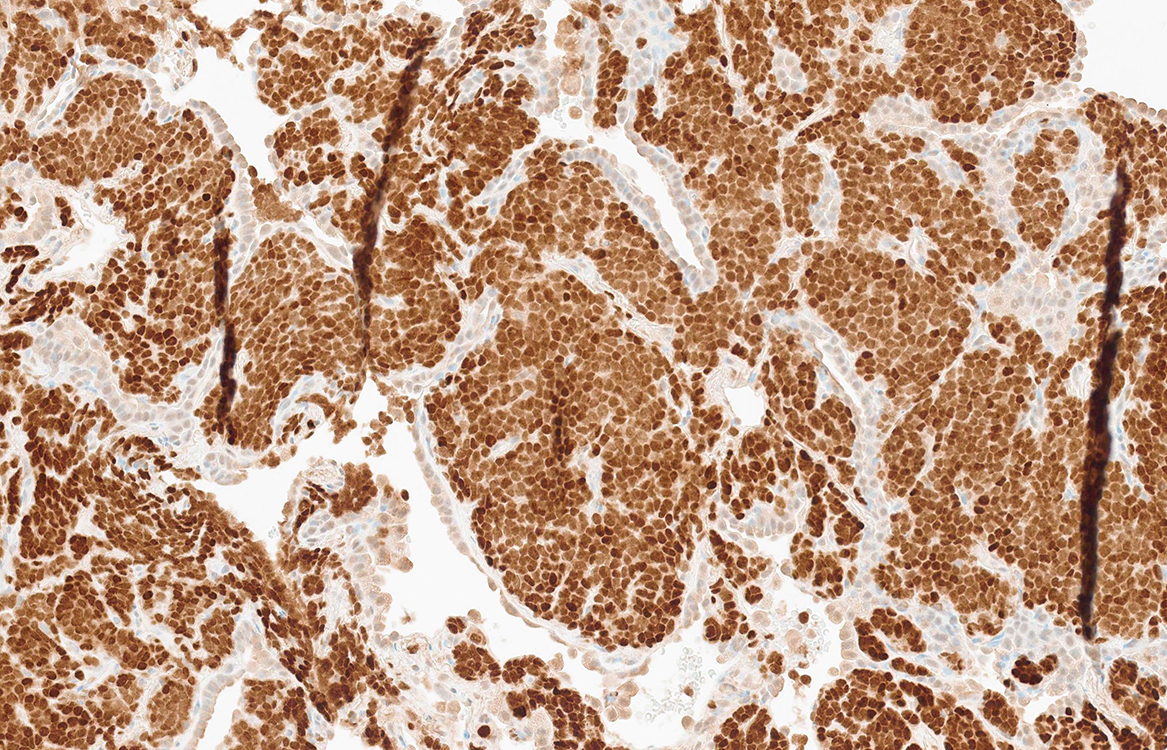

Figure 5 (NKX2.2)